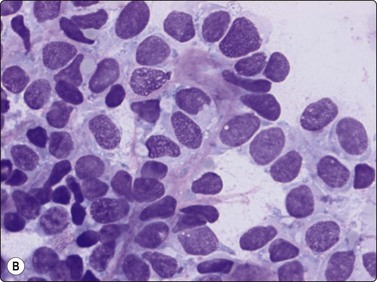

Alveolar rhabdomyosarcoma is a typical small round cell malignancy in FNB smears (Fig. 15.41). Smears show predominantly single cells, and stripped nuclei are common. Alveolar or rosette-like structures may be seen. The cells are mainly uniform with rounded or irregular nuclei and scanty cytoplasm. In almost every case, small rounded or pear-shaped cells with eccentric nuclei and eosinophilic cytoplasm are found (Fig. 15.42). The chromatin is variably coarse and nucleoli may be prominent. The multinucleated cells with small, dark nuclei, commonly seen in histologic sections are, in our experience, not a common finding in smears (Fig. 15.43).

image

Fig. 15.41 Alveolar rhabdomyosarcoma

The cells are mainly uniform with rounded or irregular nuclei and scanty cytoplasm (H&E, IP).

Fig. 15.42 Alveolar rhabdomyosarcoma

In almost every case, small rounded or pear-shaped cells with eccentric nuclei and eosinophilic cytoplasm (small rhabdomyoblasts) are found (H&E, HP).